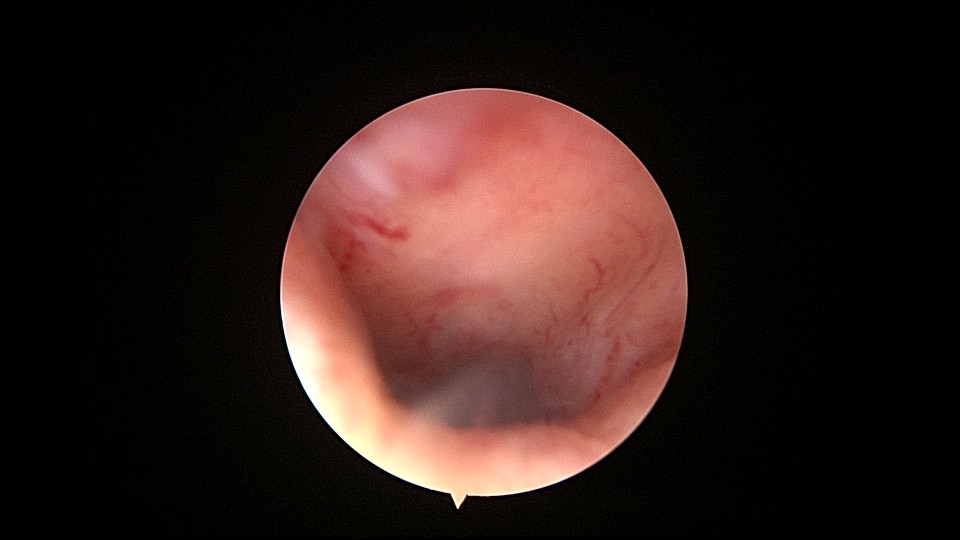

患者55岁,G1P1,顺产1次。安环34年,闭经半年,2天前外院取环失败,感下腹疼痛不适。术前复查B超,子宫前壁肌瘤直径4cm,宫内节育器回声。术中见子宫前倾后屈位,宫颈外口见息肉,镜鞘旋转扩宫进入宫腔,O型环位置正常,宫腔右前壁见直径2.5cm肌瘤结节突向宫腔,取环钩顺利取出节育环,宫腔无其他异常。该患者常规取环时未膨宫,子宫位置特殊,加之子宫受刺激后肌瘤凸向宫腔,可能对取环器械形成支点及杠杆效应,取环器械难以到达节育环位置,导致取环失败。